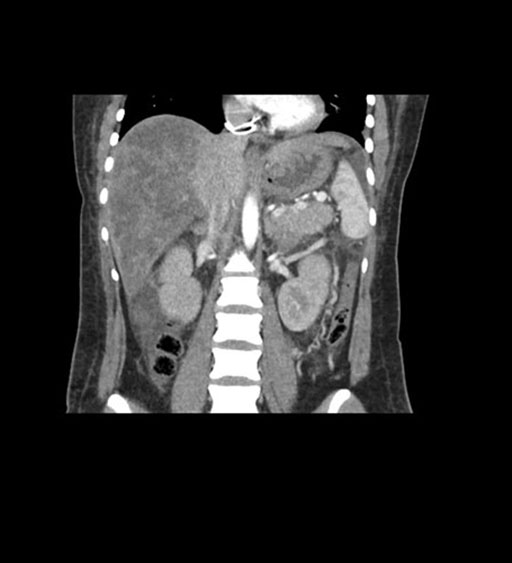

Imaging Analysis

Look through the patient's CT scan to identify any areas of concern for the necessary procedure.

Coronal Arterial

Coronal Venous

Based on initial findings, which issue(s) would you be most concerned about?